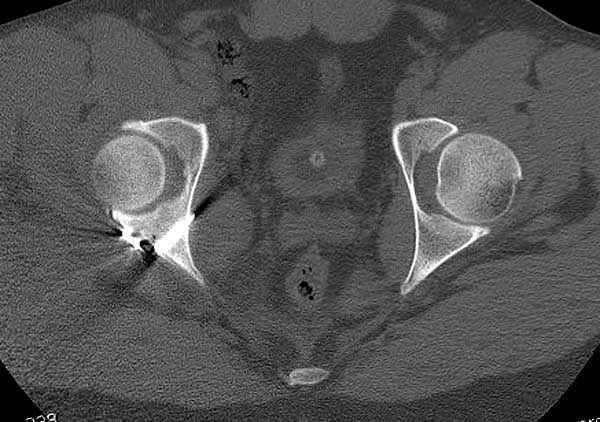

Кроме вывиха виден перелом задней стенки, насчет задней колонны не уверен (видна линия перелома дистальнее ацет. крыши - подвздошная проекция или СТ помогли бы прояснить ситуацию). Поэтому с такой ситуации только закрытое вправление без рефиксации фрагмента задней стенки может привести к рецидиву вывиха (с чем имел неприятность столкнуться не так давно).

На первый взгляд, бедро надо вправить, наложить вытяжение, и дообследовать - Judet views, CT вертлужной впадины, чтобы оценить дефект задней стенки. Вероятно, придется делать остеосинтез заднего края.

5:24 Рентгенограмма таза, вызывают врача ортопеда (снимок N1), его диагноз: закрытый переломо-вывих правого тазабедренного сустава, получает добро на закрытую репозицию в приемном отделении

5:38 Дважды неудачная попытка закрытой репозиции в приемном отделении

N 2